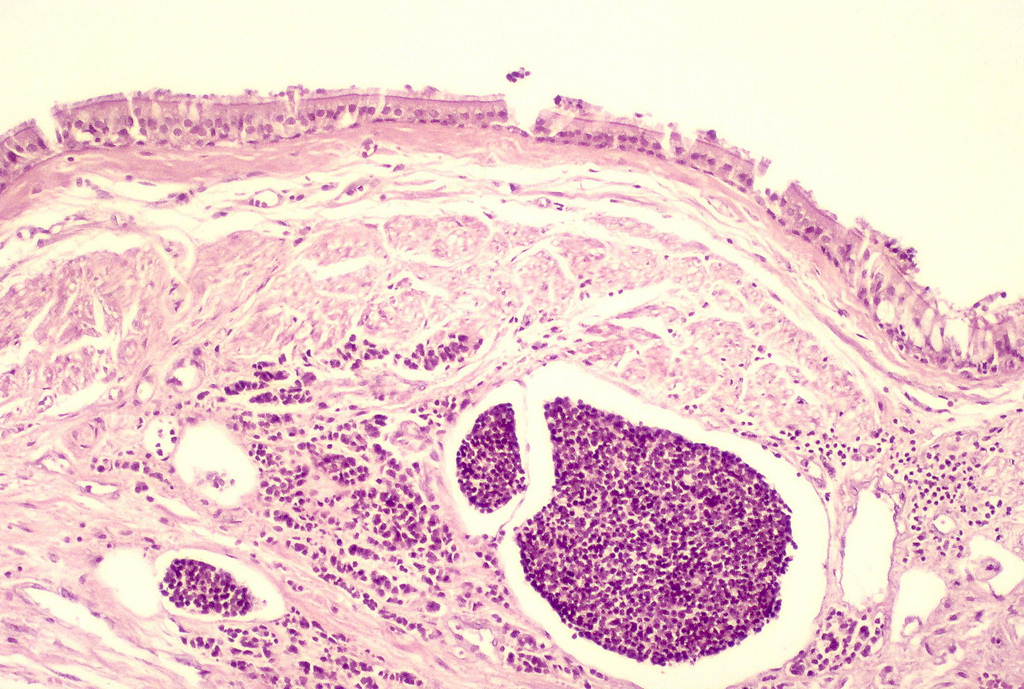

A microscope image of a cancerous tumour (stained in dark purple) taken from a tissue sample. Source: Flickr. Author: Yale Rosen. Image licensed by CC BY-CA 2.0